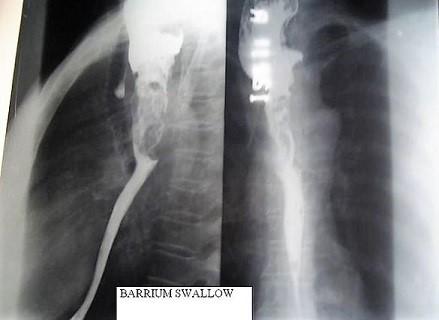

Barium swallow

In this test you drink some barium liquid. The barium liquid is often fruit-flavoured so it is pleasant to drink. You stand in front of an X-ray machine whilst X-ray pictures are taken as you swallow. This test aims to look for problems in the gullet.

These include a narrowing (stricture), hiatus hernias, tumours, reflux from the stomach, disorders of swallowing, etc. You will usually be asked not to eat or drink for a few hours before this test. A barium swallow test takes about 10 minutes.

Barium swallow X-ray

By Netha Hussain (Own work) via Wikimedia Commons